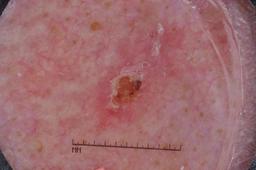

{

"age_approx": 70,

"anatom_site_general": "upper extremity",

"concomitant_biopsy": true,

"dermoscopic_type": "contact non-polarized",

"diagnosis_1": "Malignant",

"diagnosis_2": "Malignant epidermal proliferations",

"diagnosis_3": "Squamous cell carcinoma, NOS",

"diagnosis_confirm_type": "histopathology",

"image_type": "dermoscopic",

"lesion_id": "IL_1742886",

"melanocytic": false,

"sex": "male"